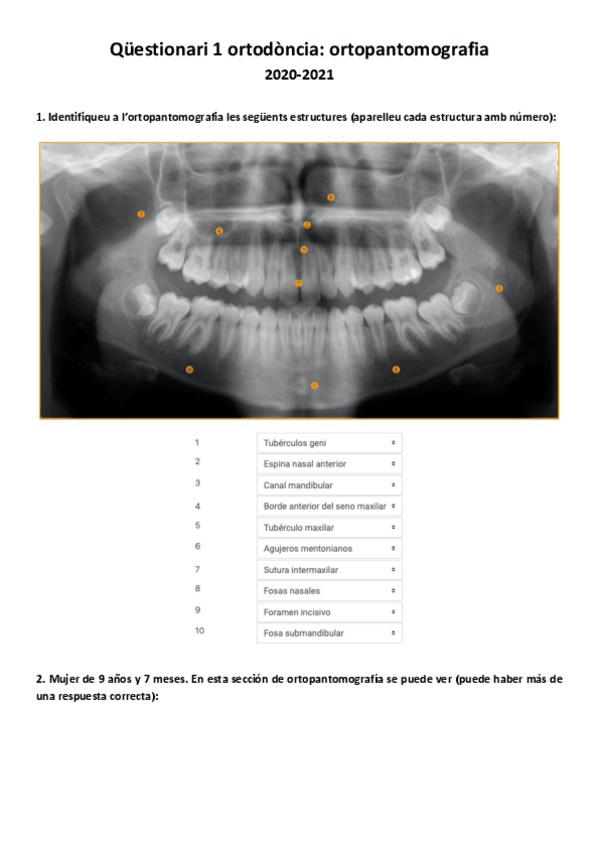

Questionari-1-ortodoncia.pdf